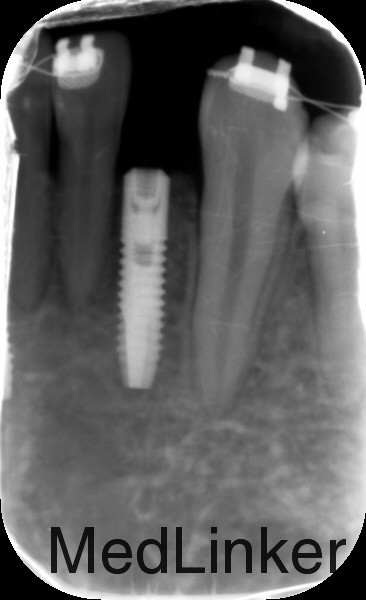

检查:下侧切牙双侧缺失,缺牙间隙约有1cm,其余无特殊 全景片示:下侧切牙双侧缺失

治疗:1、联合正畸科治疗,正畸科移动双侧中切牙至中线两侧后留出位置行种植治疗 2、常规消毒铺巾局部麻醉,切开翻瓣,植入Astra种植体3.0*8mm种植体两枚,严密缝合